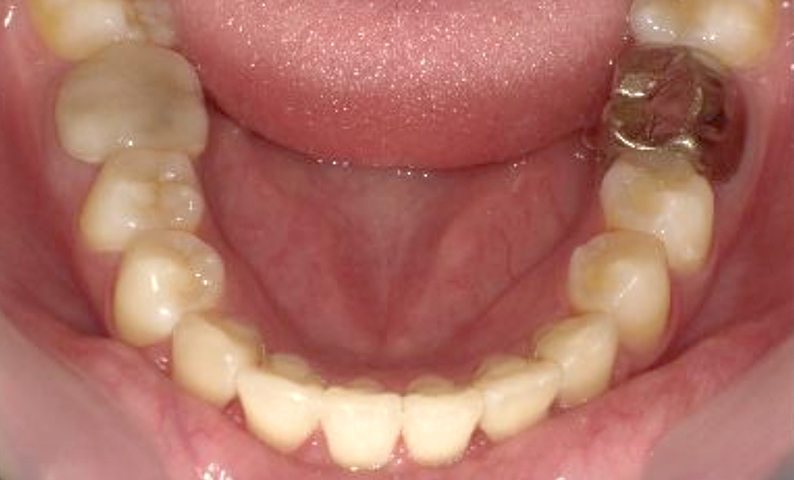

「20代の症例集」:下顎の症例

症例_004 下顎だけの部分矯正

治療期間:7ヶ月金額:24万円+税男性前歯のガタガタ下の前歯だけ

| Before | After |

|---|---|

|